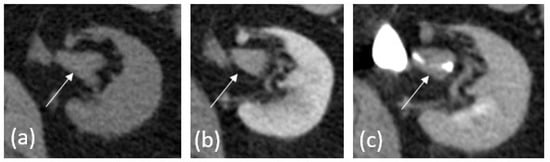

2.2. Computed Tomography

- Raman, S.P.; Fishman, E.K. Upper and lower tract urothelial imaging using computed tomography urography. Urol. Clin. N. Am. 2018, 45, 389–405. [Google Scholar] [CrossRef] [PubMed]

- Ali, O.; Fishman, E.K.; Sheth, S. Upper urinary tract urothelial carcinoma on multidetector CT: Spectrum of disease. Abdom. Imaging 2019, 44, 3874–3885. [Google Scholar] [CrossRef] [PubMed]